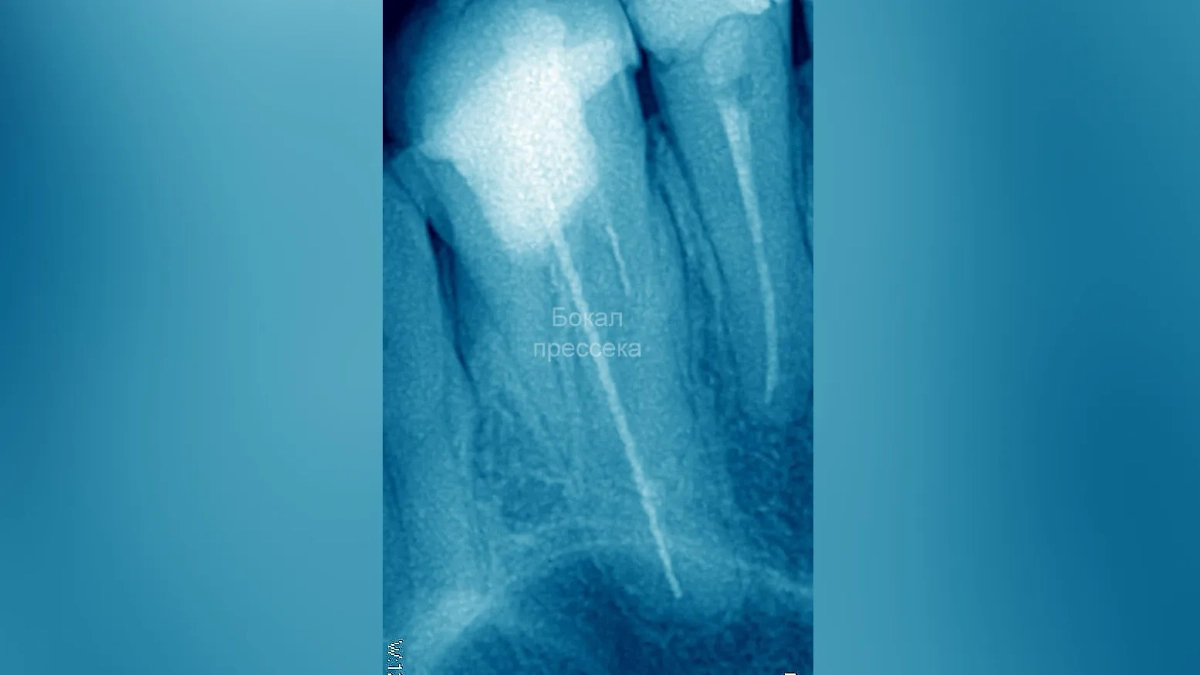

Женщина ходила с иглой в зубе. Обложка © Telegram / Бокал прессека

Длина иглы составляла около двух сантиметров. Её смогли найти только благодаря рентгеновскому снимку. Женщина вообще ничего не знала об инородном теле и никогда не жаловалась на какие-либо проблемы с зубами. При каких обстоятельствах игла попала в рот, неизвестно. После обнаружения её успешно удалили.